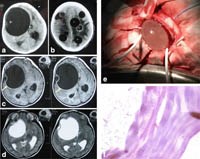

Hình 10. Một số tổn thương do Echinococcus granulosus dễ chẩn đoán nhầm với bệnh lý khác